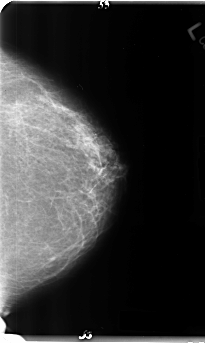

B_3146_1.LEFT_CC

LEFT_CC LINES 4800 PIXELS_PER_LINE 2864 BITS_PER_PIXEL 12 RESOLUTION 50 NON_OVERLAY